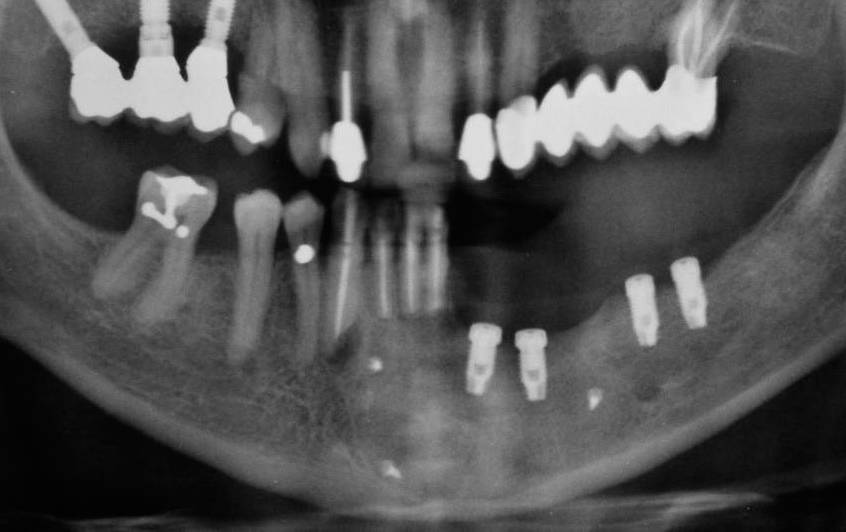

L’elemento diagnostico fondamentale è l’esame radiografico delle arcate dentarie e in generale del massiccio facciale (RX ortopanoramica, RX endorali).

La presenza di una ciste è evidenziata da un’area di radiotrasparenza dovuta all’erosione ossea. Nelle cisti germinali o follicolari sarà visibile anche l’elemento dentario incluso. Nel caso di una cisti radicolare sarà presente un dente con necrosi pulpare oppure dei residui radicolari. In alcuni casi il dente può non essere presente (cisti residue).

Per le cisti localizzate nel mascellare superiore è opportuno effettuare anche uno studio radiografico e TC del cranio al fine di stabilire i rapporti che la formazione cistica assume con il seno mascellare e con le altre strutture ossee del massiccio facciale.